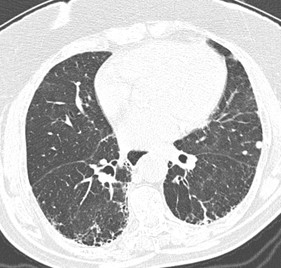

Figura 1A e B: Paciente com fibrose pulmonar idiopática mostrando franca progressão da doença nos exames de imagem de seguimento com diferença de 1 ano. Note a maior extensão do reticulado, bronquiectasias, bronquiolectasias e do faveolamento em B.

A definição de progressão radiológica da fibrose pulmonar pode consistir na avaliação visual e quantitativa da imagem. Na avaliação visual, é realizada a análise comparativa da quantidade de acometimento em todos os campos pulmonares observando-se os eixos axial, coronal e sagital, considerando-se os exames iniciais e de seguimento. O aumento na extensão da fibrose é considerado progressão. A progressão radiológica pode ser representada por aumento na extensão das bronquiectasias e bronquiolectasias de tração, novas opacidades em vidro fosco com bronquiectasias de tração, novo reticulado fino ou aumento do componente grosseiro, faveolamento novo ou aumento do faveolamento inicial, além de aumento na redução volumétrico do lobo acometido(1).